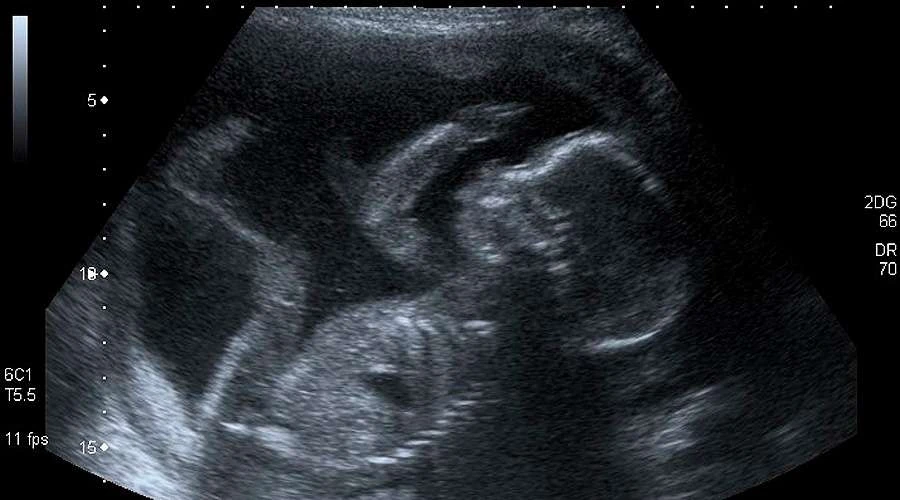

Las madres pueden empezar a sentir los golpes de sus bebés desde las 16 semanas de gestación, aunque algunos movimientos espontáneos comienzan a las siete semanas.

Según indicó LiveSciense, el estudio sugiere que con cada golpe o patada –conocidas como movimientos fetales– el bebé construye una red cerebral básica que le permite entender qué parte del cuerpo se está moviendo y cómo se toca.